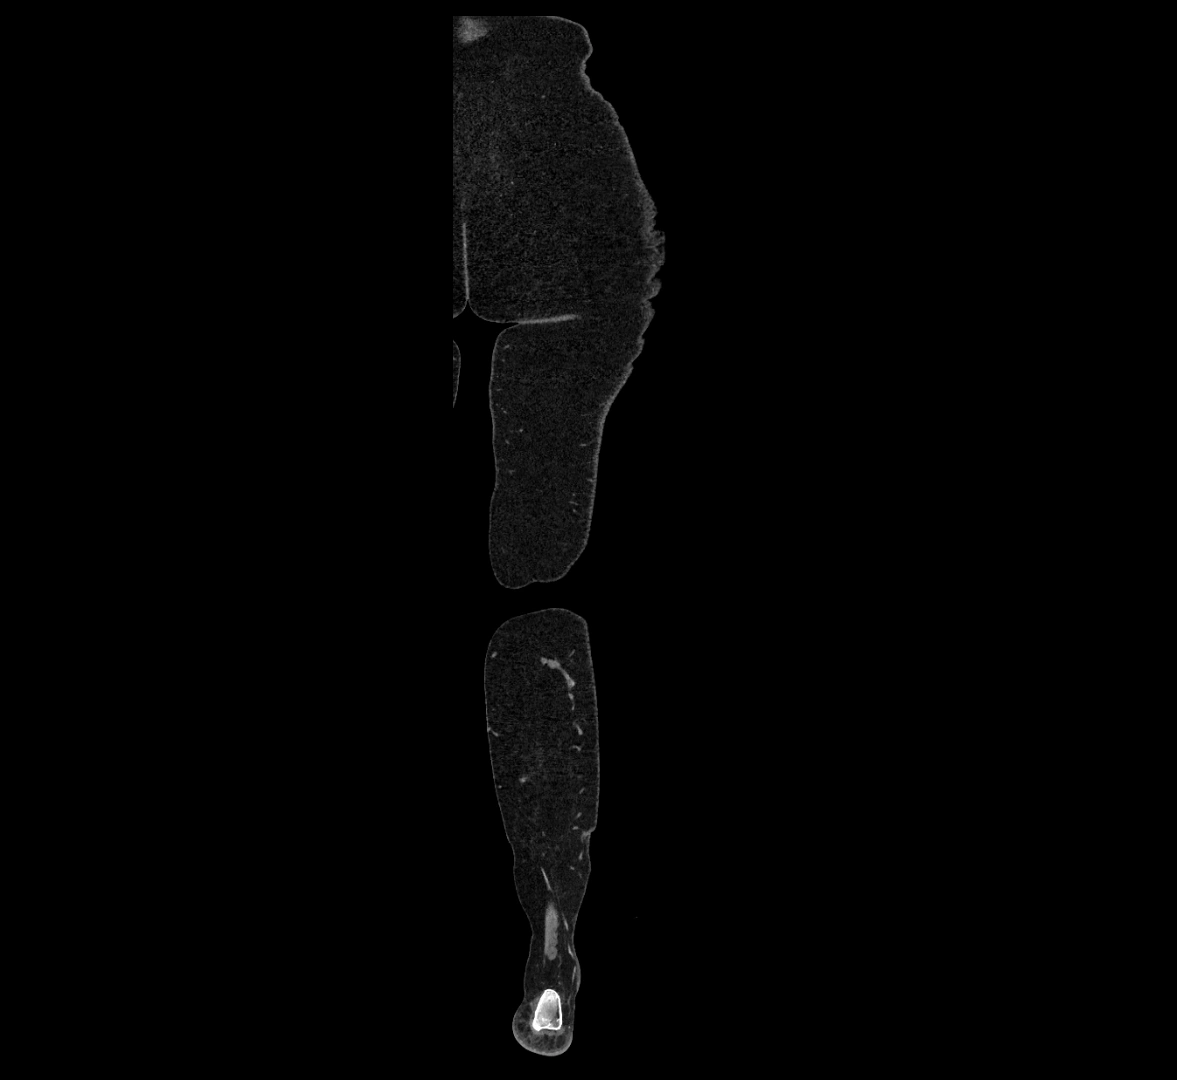

CT images

image